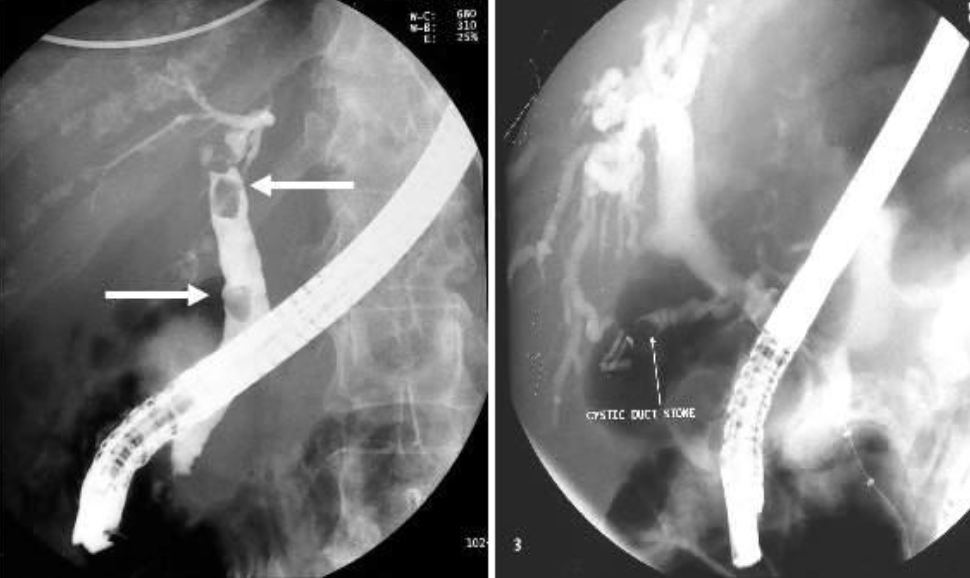

Stone in CBD ERCP study

Acute abdomen presentation